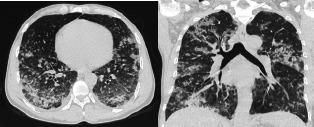

Varicella pneumonia is uncommon among adults and can present as potentially life-threatening complications of varicella. Here we report a case of a 43-year-old man with no known history of chronic disease and no allergic history who presented to our hospital emergency department with widespread skin eruptions over the entire body and hemoptysis. Varicella pneumonia was diagnosed based on the patient being in contact with his 6-year-old son who had contracted chickenpox 10 days back, typical cutaneous lesions, pulmonary symptoms and radiographic findings. The patient was treated with oral acyclovir and was admitted to the intensive care unit for monitoring. The patient recovered completely after 10 days of treatment.

成人水痘肺炎并不常见,但可出现水痘的潜在危及生命的并发症。在此,我们报告一例 43 岁男性病例,该患者无已知慢性病史,无过敏史,因全身广泛皮疹和咯血就诊于我院急诊科。根据患者与 10 天前患水痘的 6 岁儿子接触的病史、典型的皮肤损伤、肺部症状和影像学发现,诊断为水痘肺炎。患者接受阿昔洛韦口服治疗,并收入重症监护病房进行监测。经过 10 天的治疗,患者完全康复。